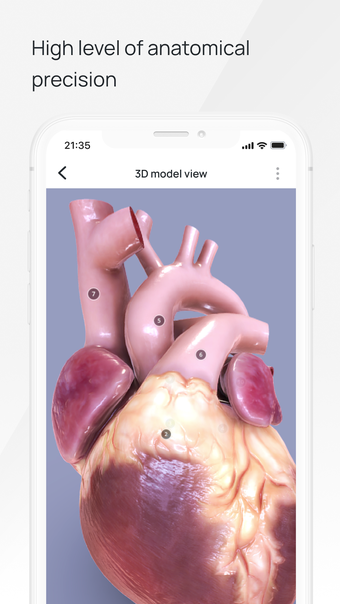

All 3D pathology models are developed in close cooperation with medical experts of hospitals and research centers. They are thought out to the very smallest detail. Each category contains models of healthy organs.